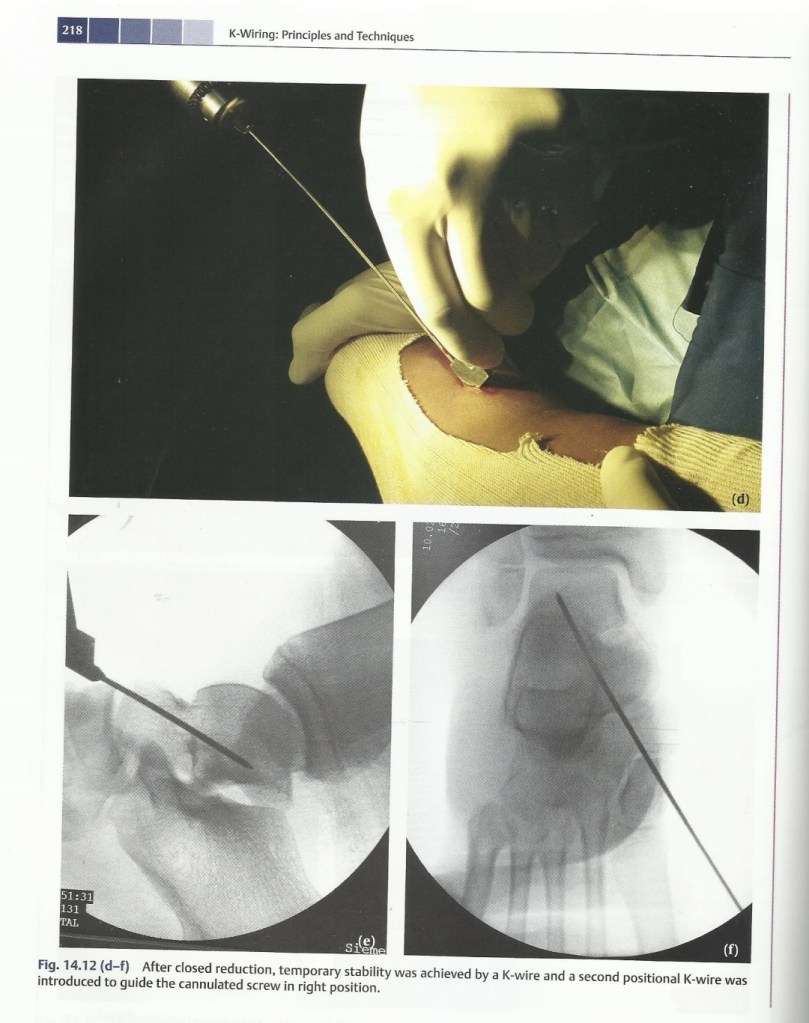

Talus fracture & Subtalar dislocation